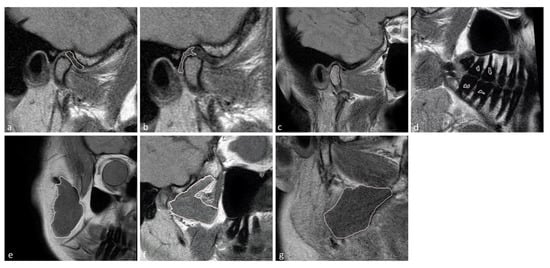

The temporomandibular disk, retrodiscal tissue, condylar bone marrow, masseter muscle, lateral pterygoid muscle medial pterygoid muscle, and dental pulp of the first and second molars were manually segmented by the dentist. The segmentation was performed twice at an interval of two months, with manual contour tracing using the VisNow Plugin Medical library [20] (Figure 1). Segmentation was performed on all slices containing the relevant structure. Due to missing molars, segmentation and further analysis of the pulp was not possible in eight joints. The intrarater reliability was assessed with the intersection-over-union measure. The average of two measurements was taken into consideration in further statistical analysis.

Figure 4. Short fraction components for the (a) disk; (b) retrodiscal tissue; (c) bone marrow of the condyloid process; (d) pulp; (e) m. masseter; (f) m. pterygoideus lateralis; and (g) m. pterygoideus medialis. (h) Color scale showing the reference values.